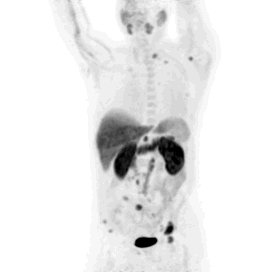

Gewebever­änderungen werden in der PET-CT Aufnahme durch die erhöhte Anreicherung klar erkennbar.

Für das PET-CT wird dem Patienten ein radioaktiv markierter Traubenzucker injiziert. Dieser verteilt sich im Körper, wobei krankhafte Gewebe einen erhöhten Stoffwechsel haben und damit mehr der Injizierten Substanz aufweisen. Diese Verteilung im Körper wird nun mit der CT anatomisch im Körper exakt zugeordnet.